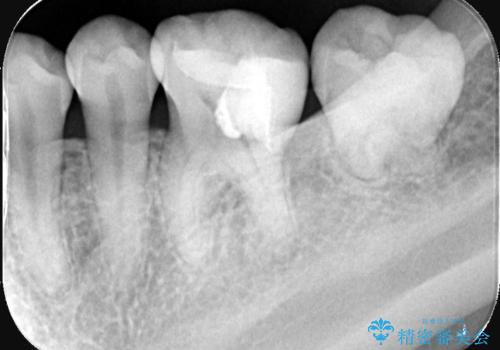

実際の治療ではVPTを施行し、その後痛みなどの症状もなく経過は良好でしたので、最終的にセラミックインレーによる修復を行いました。

生活歯髄療法(VPT)とは、本来であれば虫歯除去中に神経(歯髄)が露出した場合、すべての神経を取り除く「抜髄処置」が必要になります。しかし、術前の検査結果や、顕微鏡下で確認した神経の状態・出血の様子などをもとに判断し、バイオセラミックという生体親和性の高い材料を使用して、汚染された部分の神経のみを除去し、健康な神経は残すことができる治療法です。

この治療によって、神経を保存しながらも、神経のある歯と変わらない機能を保つことが可能になります。

また、長期的に神経を保存していくためには、適合性が高く、経年劣化しにくい材料を使用することが重要です。今回はそうした観点から、セラミックインレーで最終的な修復を行いました。